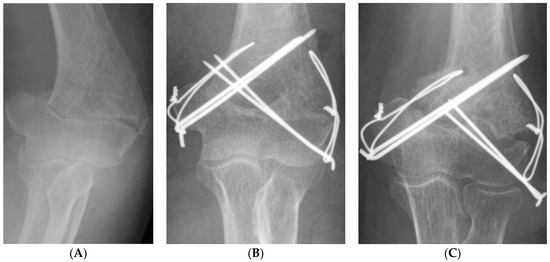

A multivariate logistic regression analysis showed that combined fracture operation (odds ratio 10.467; 95% CI 1.880–58.257; p = 0.007) and TBW (odds ratio 9.176; 95% CI 1.474–57.135; p = 0.018) were independent risk factors for non-union after ORIF in distal humerus fracture (Figure 3 and Table 5).

Figure 3.

A 67-year-old female patient with non-union after ORIF due to distal humerus fracture with usage of tension band wiring as the fixation method (A) pre-operative simple radiograph, (B) immediate post-operative simple radiograph, (C) a non-union was observed in the simple radiograph 7 months after the surgery.